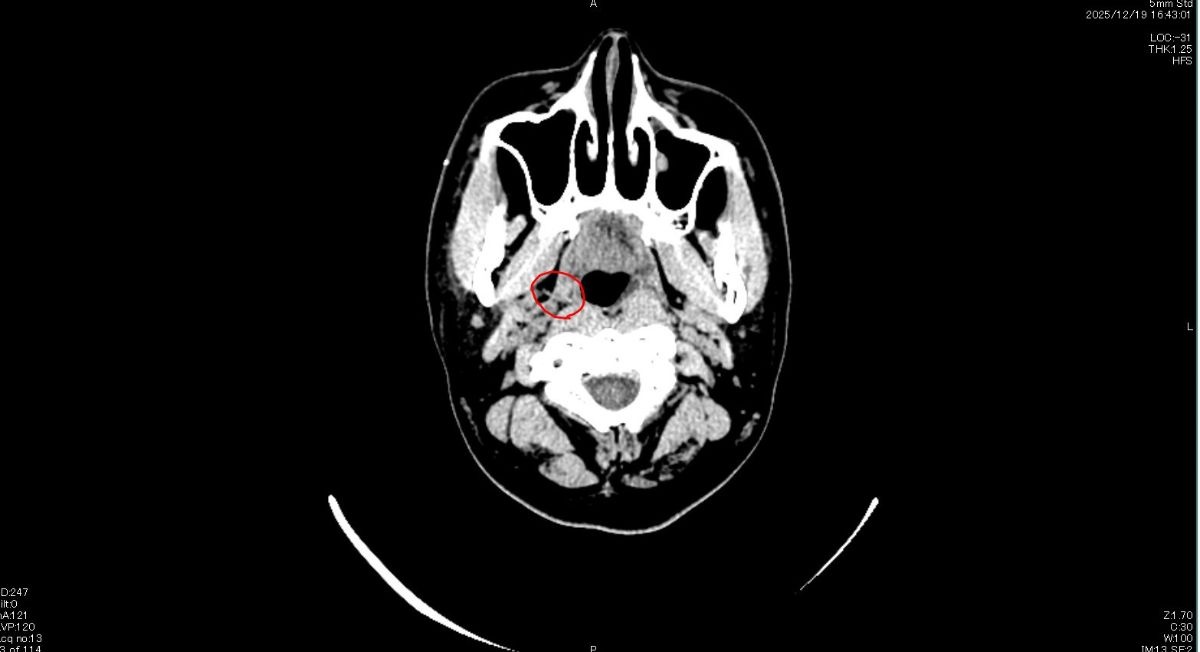

魚の骨(アジ)が刺さったんだけど医者に行っても見当たらない、CT撮ってもこれは魚の骨じゃないって言われるんだよ

そうCTに写っている位置と痛みがある位置が感覚では一致してる

でもこんなところに魚の骨があるわけないって言われて取る形もしてもらえないんだ…

赤丸のとこは普通に扁桃だよ

画像診断ではなにも問題ない

魚の骨はCTなんかには映らないことも多いしね

目視で見てくれたり、経験の多い耳鼻咽喉科に行ってみな

CTのは魚の骨じゃないってこと?